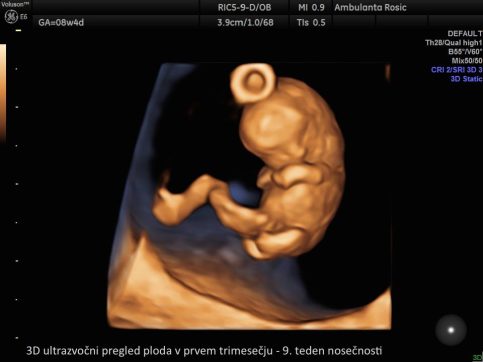

3D/4D ultrazvočni pregled ploda

Bodoči starši želite čimprej spoznati svojega malčka. To nam omogoča 3D/4D ultrazvočni pregled ploda, pri katerem z našim vrhunskim ultrazvočnim aparatom posnamemo 3D sliko ploda, četrta dimenzija (4D) pa doda še gibanje.

S pregledom opazujemo plodov razvoj, gibanje, pogledamo obraz in vam s tem omogočimo čustveno povezavo z otrokom.

V prvem trimesečju lahko 3D/4D ultrazvočni pregled ploda opravimo ob prvem pregledu ali hkrati z meritvijo nuhalne svetline. Pri 3D/4D ultrazvoku v drugem in tretjem trimesečju nosečnosti določimo tudi lego ploda, položaj posteljice, količino plodovnice, preverimo rast in telesno težo ploda, izmerimo pa lahko tudi pretoke skozi popkovnične žile z Dopplersko ultrazvočno preiskavo za oceno stanja ploda. 3D/4D ultrazvok ploda lahko opravimo tudi ob morfologiji ploda.

3D/4D ultrazvok v nosečnosti izvajamo z vaginalnim (nožničnim) ali abdominalnim (trebušnim) tipalom. Vaginalno tipalo uporabljamo pri ultrazvočni preiskavi v prvem trimesečju, abdominalno tipalo pa v drugem in tretjem trimesečju nosečnosti. S tem imate pri nas nosečnice možnost opraviti 3D/4D ultrazvok ploda že od prvega pregleda v nosečnosti dalje.